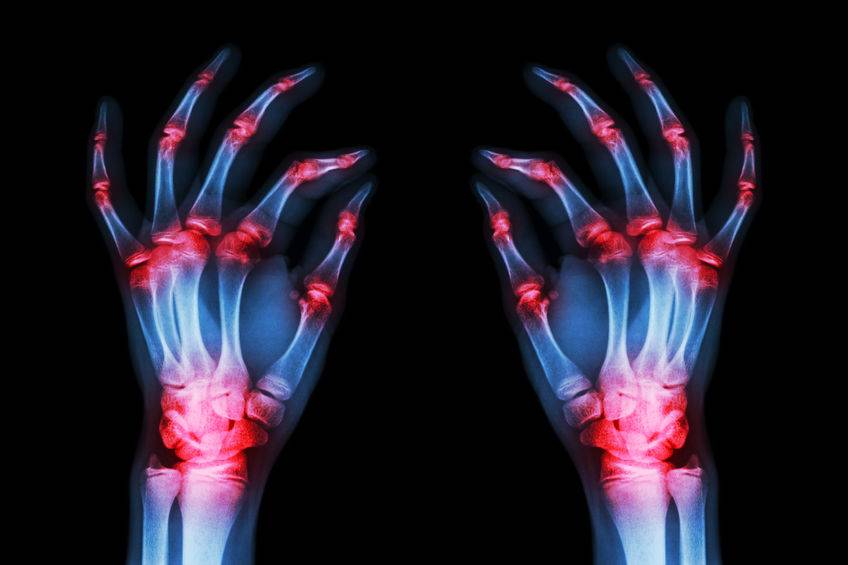

痛风是由人体内尿酸过高引起尿酸结石而产生的不适症状 , 是由人体嘌呤代谢紊乱引起的疾病 , 与日常的生活方式和饮食习惯都密切相关 。